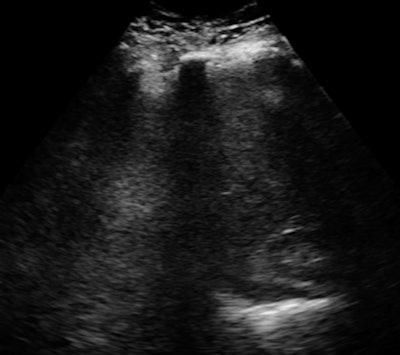

The firm has also picked the toughest patients: obese individuals for whom ultrasound has difficulty. In clinical validation studies, the InnerVision technology has been able to demonstrate anatomical structures deep in the body in patients with body mass indexes as high as 66. By showing its expertise in these patients, InnerVision should be able to excel in any other area, the company believes.